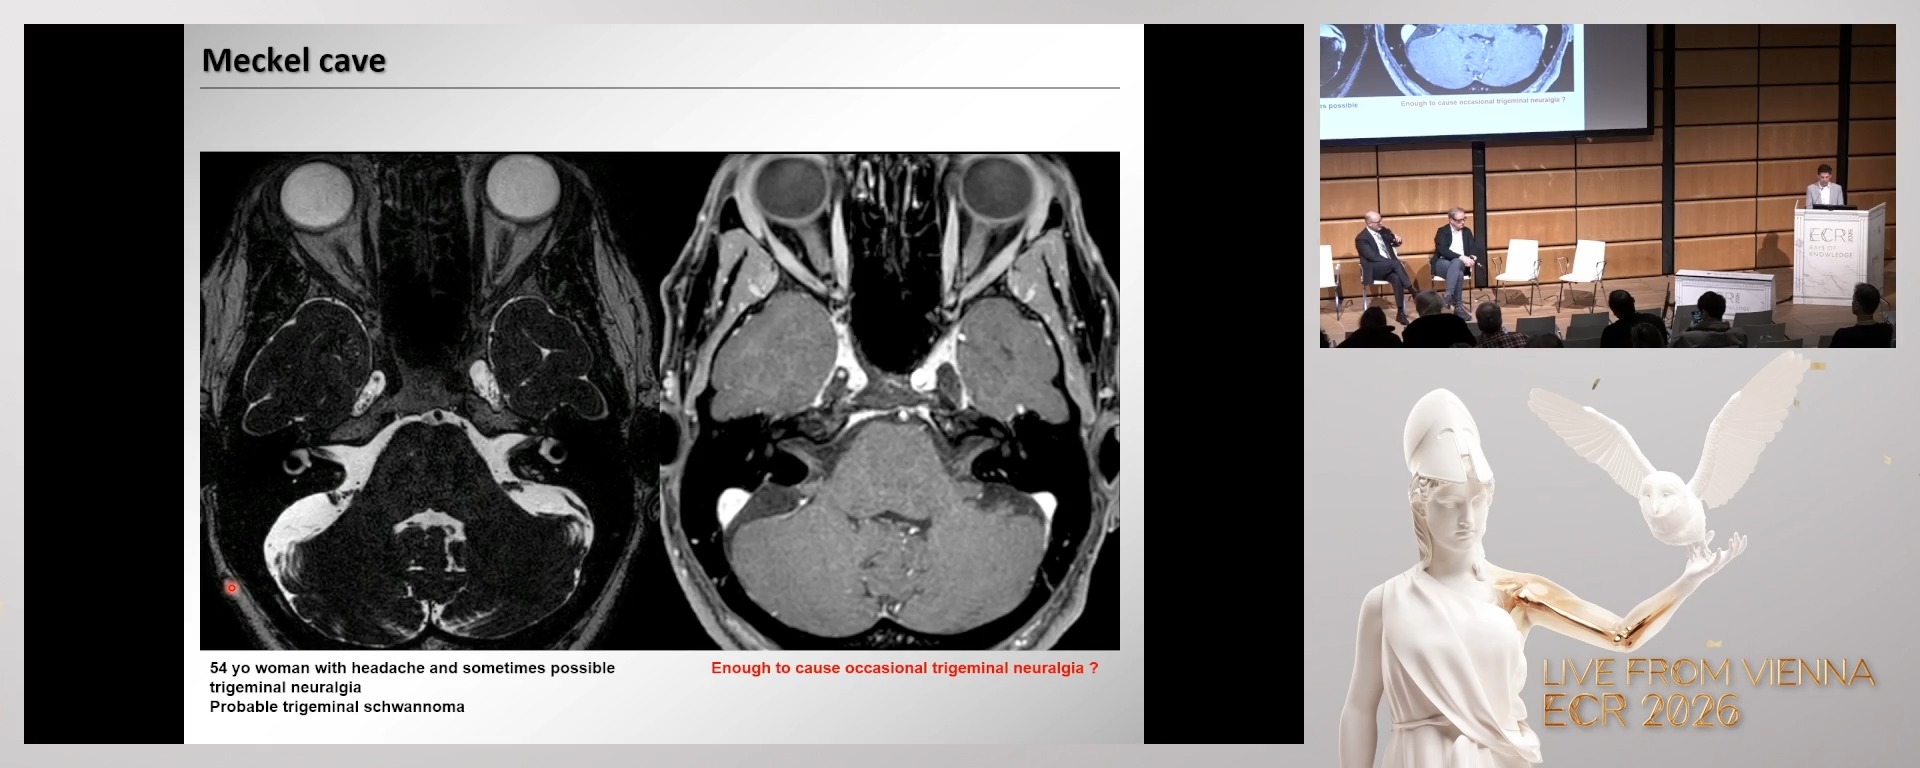

Neuroimaging in headache part II: findings outside the brain associated with headache

Sven Haller, Geneva / Switzerland

1. To review imaging findings of neurovascular compression syndromes, notably trigeminal neuralgia.